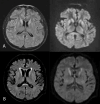

Description of the cases: A series of 6 cases with a probable diagnosis of sporadic CJD, treated in a Peruvian national reference hospital, are presented.

Clinical findings: The relevant clinical signs were rapidly progressive dementia and myoclonus, followed by akinetic mutism and pyramidal signs.

Treatment and results: Of the cases presented, 80% were men, with an average age of presentation of 65 years and duration from diagnosis to death of 6.5 months. Laboratory tests, images (Brain Resonance) and protein dosage 14.3.3 were performed to support the clinical suspicion. There is no effective treatment at the moment for said pathology.